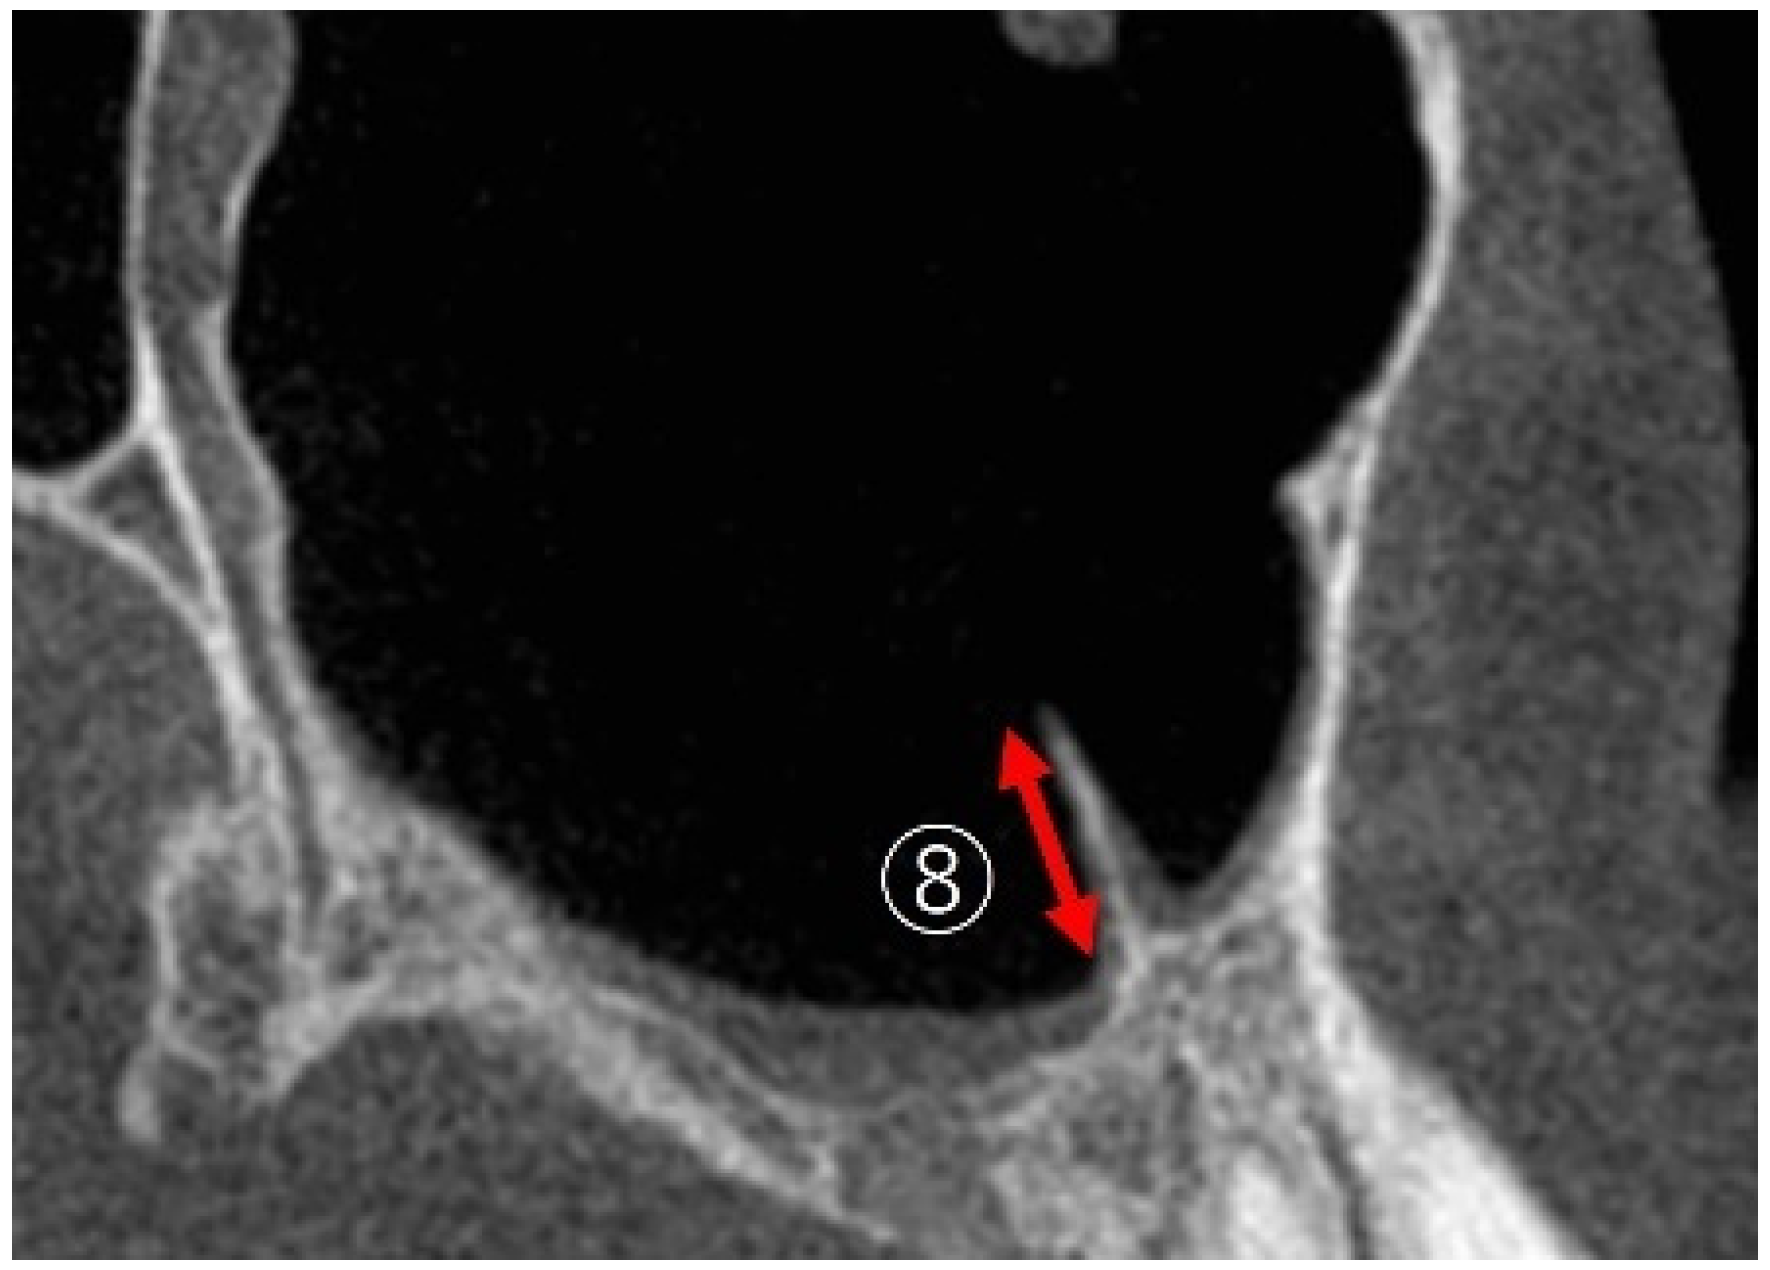

2.2. Measurement Method Using CBCT Images

2.3. Measurement Items

2.3.2. Measurement of PNR Angle and Maxillary Sinus Angle (MSA)